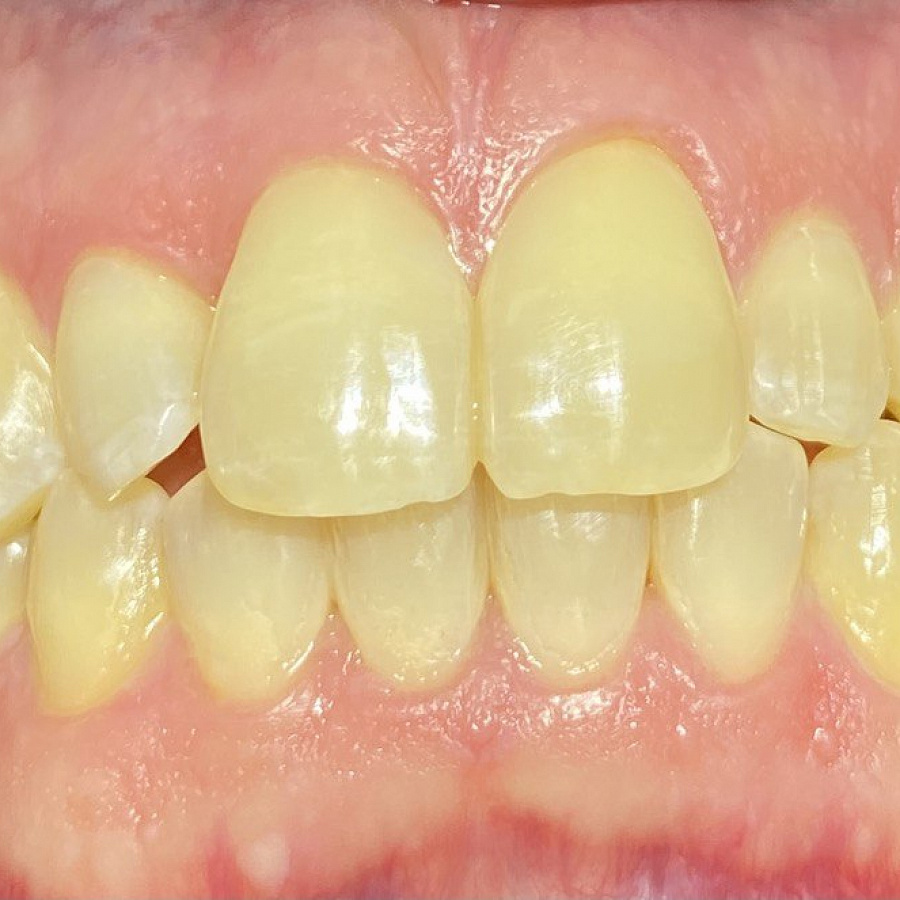

Пациент обратился с жалобами на неровные передние зубы верхней и нижней челюстей.

сужение зубных рядов,

обратное перекрытие в области фронтальных зубов слева,

разворот по оси передних зубов верхней и нижней челюстей,

стираемость эмали зубов,

индивидуальную микродентию 12 и 22 зубов.

Ортодонтическое лечение с помощью элайнеров длилось 10 месяцев. Далее последовало протезирование и установка виниров.

Результат лечения